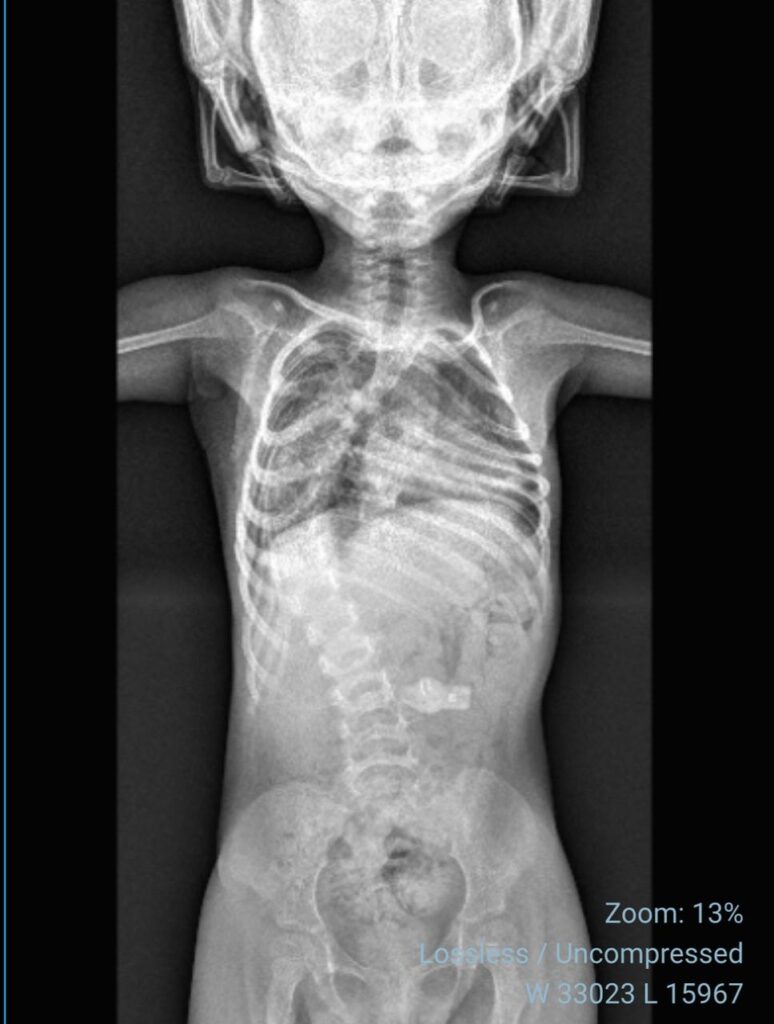

La familia de Sofía, una niña de cuatro años diagnosticada con Atrofia Muscular Espinal (AME), ha puesto en marcha una campaña solidaria con el objetivo de reunir los fondos necesarios para una cirugía de columna de carácter urgente. La menor presenta una escoliosis severa, condición asociada a su diagnóstico base, que requiere intervención quirúrgica para evitar un mayor deterioro en su salud y calidad de vida.

De acuerdo con la información entregada, la progresión de la escoliosis hace necesaria una intervención temprana para evitar complicaciones respiratorias y funcionales. Por ello, la familia solicita apoyo tanto económico como en la difusión de la campaña.